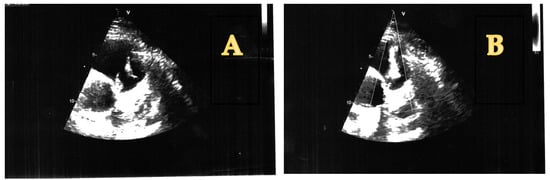

2. The Case